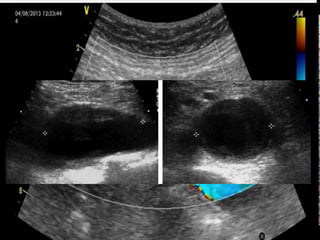

• #32 -La vesícula nos la podemos encontrar de forma que la veamos más fácil o más difícilmente. En el mejor de los casos (son las vesículas “chupadas de ver”), simplemente haciendo un barrido por el reborde costal derecho nos la podemos encontrar. Si no la encontráramos de ésta forma, le pediremos al paciente que haga una inspiración profunda (así la vesícula desciende por debajo del reborde costal). Si el paciente no colabora (sobre todos los pacientes mayores, los “Don”), y no respira profundamente bien, habrá que hacer una exploración intercostal (en éste caso trazamos la bisectriz del ángulo que forma nuestra mano adaptándola al reborde costal, y sobre esa bisectriz, en el espacio intercostal correspondiente, colocamos la sonda ecográfica. Es un corte parasagital derecho levemente oblicuo utilizado para observar la vesícula biliar. En esta imágen se observa la (1) vesícula biliar, el (2) LHD y la (3) vena porta junto con la (4) arteria hepática. La vesícula normal se debe ver piriforme, negra, de pared ecogénica, lisa, fina (3mm) y con refuerzo acústico posterior.